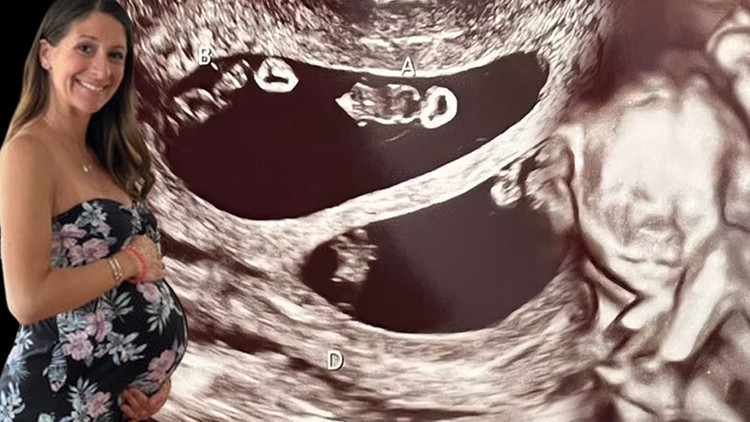

ABD'nin Massachusetts eyaletinde yer alan Taunton'dan kuaför olan 35 yaşındaki Ashley Ness, Şubat ayında rutin kontrolleri için gittiği doktorundan hamile olduğu haberini aldığında dünyalar onun onun oldu.

Ashley, 2 hafta sonra 47 yaşındaki erkek arkadaşı Val ile beraber ultrason kontrolüne gittiğinde sevinci büyük bir şoka dönüştü ve bir değil tam dört bebeğe hamile olduğunu öğrendi.

Daha önceki ilişkisinden de bir kızı olan anne adayı karnındaki dört bebeğin dördüz değil iki ayrı tek yumurta ikizi olduğunu öğrendi.

Bu keşfin ultrason teknisyenini bile şoke ettiğini anlatan anne adayı, "Taramayı ilk başlattığı zaman ekrana baktı ve 'A,B' yazdı. Durup bir an ona baktım. Görünen o ki ikizlerim olacaktı." diye sözlerine başladı ve şöyle devam etti;

"Teknisyenin kafasının karıştığını görebiliyordum. Ekranda gördüğü şeyin gerçek olup olmadığını anlamak için odadan çıkmak zorunda kaldı. Döndüğünde ise bana inanılmaz durumu anlattı. Dört bebeğe hamileydim. İki kız ve iki erkek."